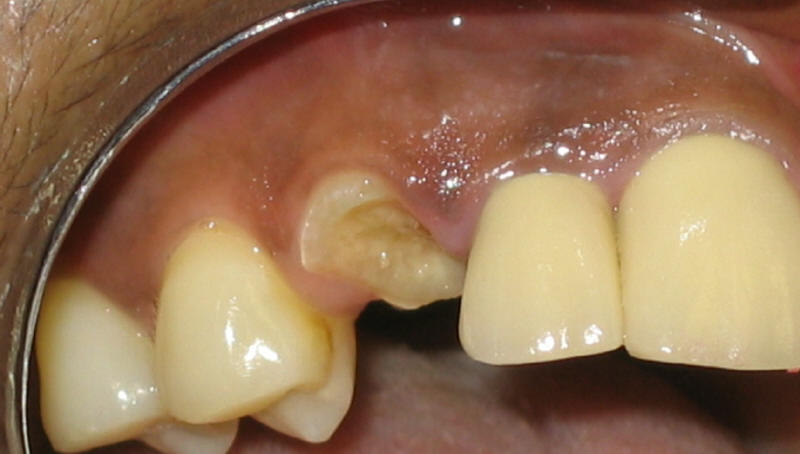

圖三:尖牙爛到牙根,黃色膿水從根管口流出 |

什么是根管治疗?根管治疗步驟如从根管里去除感染牙髓,扩大沖洗根管(圖四),然后进行充填(圖五)(105期,106期)。有些人听到根管治疗就如谈虎色变,其实根管治疗并不可怕,只要医生局麻打得好,整个治疗过程完全可以是无痛的。根管一般很细,在细小根管里操作是一个项细致工作。如果根管还弯曲(图四),治疗时间需要更长。治疗时间也与牙齿根管数量有关,一般前牙(门牙及尖牙)有一个根管,前磨牙(双尖牙)两个,磨牙三到四个。随着年龄增大,根管变细;一般来说,老年人根管治疗比年轻人难做。如果您有牙髓感染需要做根管治疗,早做比晚做容易,因为慢性牙髓感染会促使根管变细。